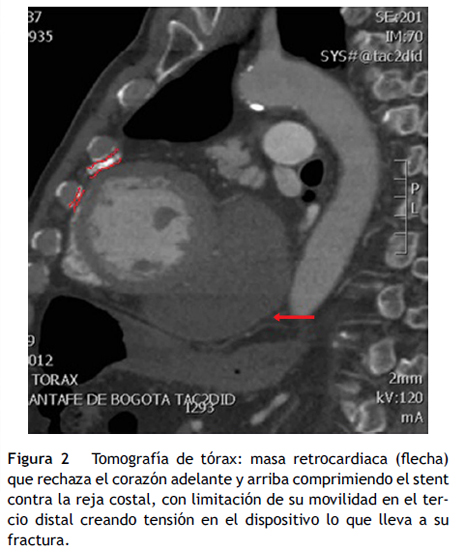

Se le realizó una tomografía axial computarizada de tórax, la cual muestra una masa retrocardiaca que rechaza el corazón adelante y arriba comprimiendo el stent contra la reja costal lo cual inmoviliza el tercio distal del stent generando el estrés mecánico sobre el dispositivo que lleva a su fractura (figs. 1 y 2).

Consideramos a este como un caso especial por que el paciente fue tratado inicialmente con un stent convencional que sufrió la restenosis (¿mismo mecanismo?) para lo cual recibió un stent medicado intra-stent (Cypher). Se presenta una noxa externa que ocasiona desplazamiento y compresión del stent entre el corazón y la caja torácica que inmoviliza la porción distal del dispositivo dejando libre la porción proximal y el punto de la fractura se encuentra exactamente en la unión de estos segmentos.